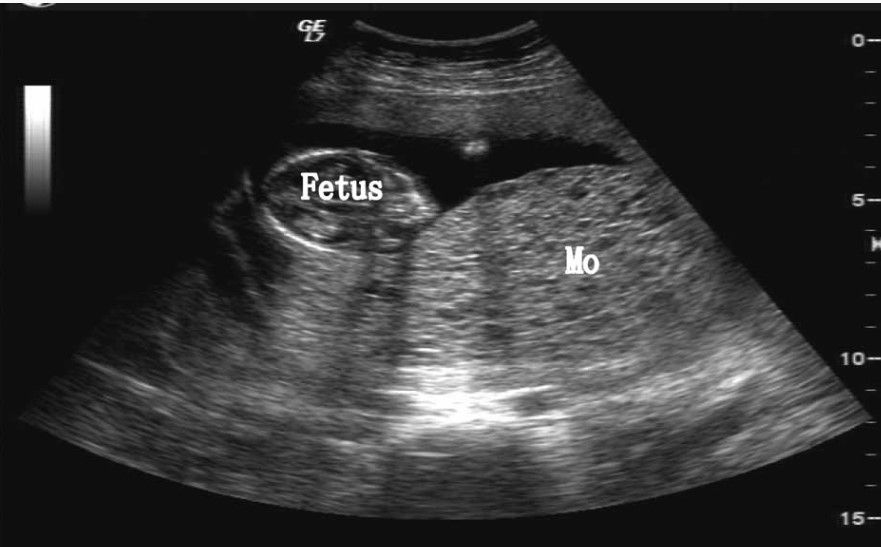

Diagnostik: sonographisch vergrösserte Plazenta (blasige Strukturen), HCG kann erhöht sein. Embryonen/Feten sind häufig nachweisbar. Diagnose erfolgt histologisch.